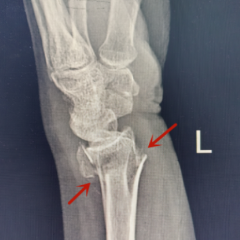

医院急诊医学科接诊后,通过询问病史及体查,考虑手腕骨折,遂立即给患者安排手腕照片检查,结果显示桡骨远端骨折,伴有明显移位。通过局部麻醉,精准手法复位及石膏外固定后,患者疼痛得到缓解,骨折复位效果满意。

左:骨折复位前;右图:手法复位后